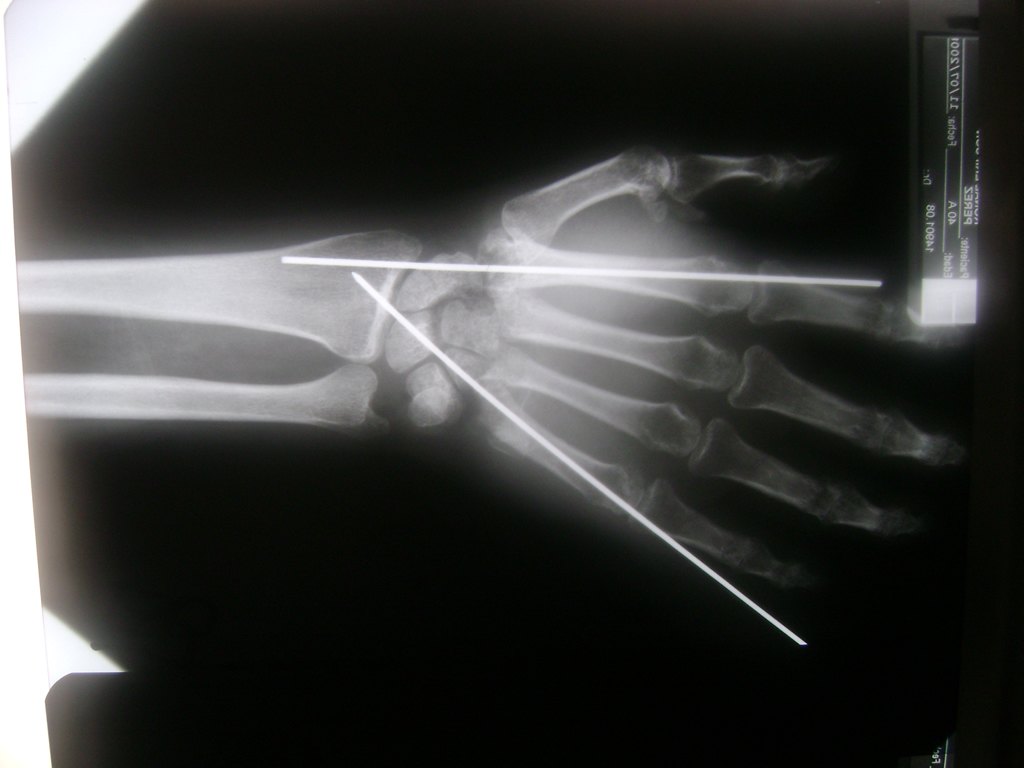

Cirugías de Calcaneo - Cirugías de Muñecas y Manos

Los procedimientos más comunes en cirugía de la mano son aquellos destinados a reparar traumatismos, incluyendo lesiones de tendones, nervios, vasos sanguíneos, y articulaciones; huesos fracturados; y quemaduras, cortes, y otros daños de la piel.